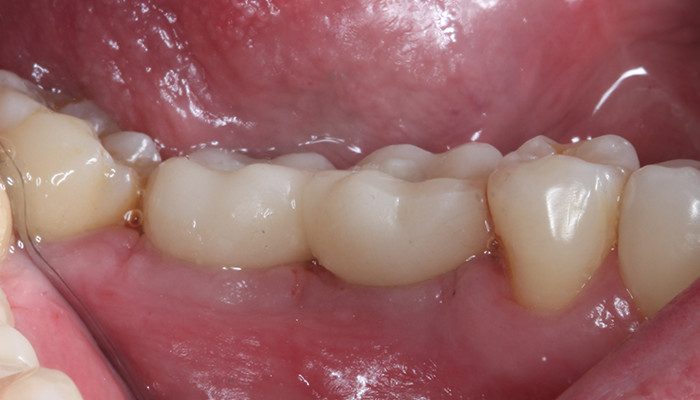

22 | Remoção de sutura e controle 10 dias de pós operatório – 46 e 47 vista vestibular.

23 | Remoção de sutura e controle 10 dias de pós operatório – Vista oclusal